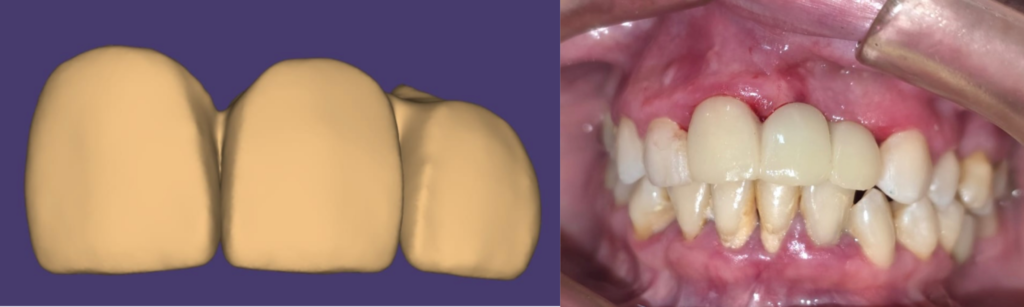

• Utilizamos un escáner intraoral para tomar impresiones digitales de la boca con los implantes ya colocados.

• Con estos datos, diseñamos y fabricamos de forma inmediata una prótesis fija provisional.

El resultado: nuestro paciente salió de nuestra clínica en Ciudad de México el mismo día de la cirugía con unos implantes seguros y una prótesis fija y estética, recuperando su sonrisa y su confianza de inmediato.